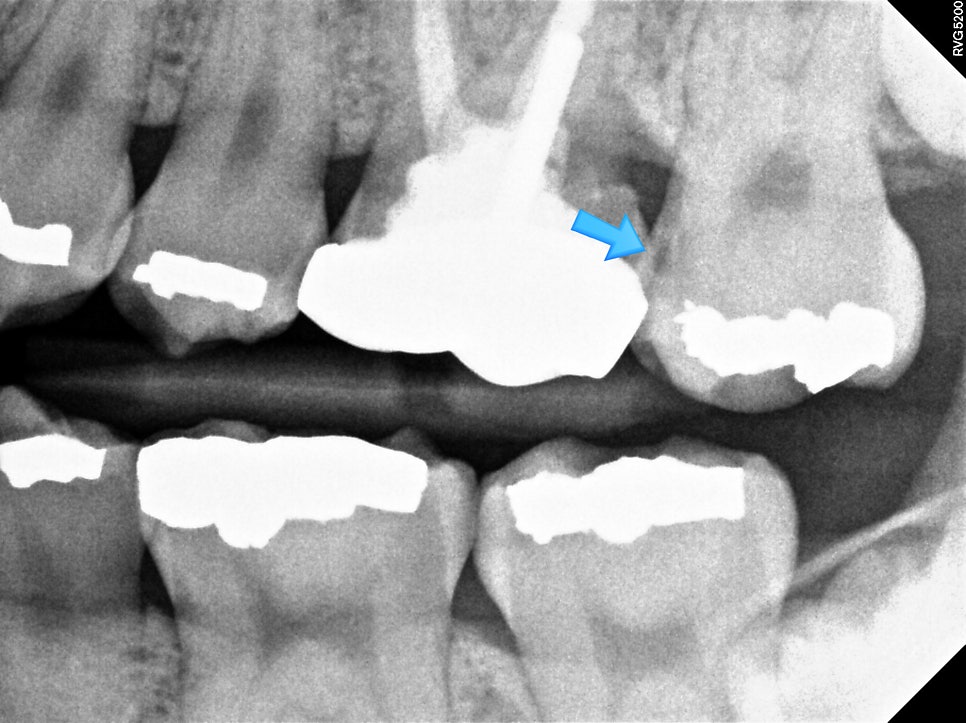

치근단 X-ray — 아말감 하방 이차 우식 의심 부위에 파란 화살표 표시된 방사선 사진

▲ 방사선 사진으로 확인한 아말감 하방 이차 우식 — 육안으로 보이지 않는 충치도 X-ray로 확인 가능

이 치아의 경우 아말감은 겉으로 양호해 보이지만, 앞쪽으로 충치가 진행된 것을 확인할 수 있습니다.